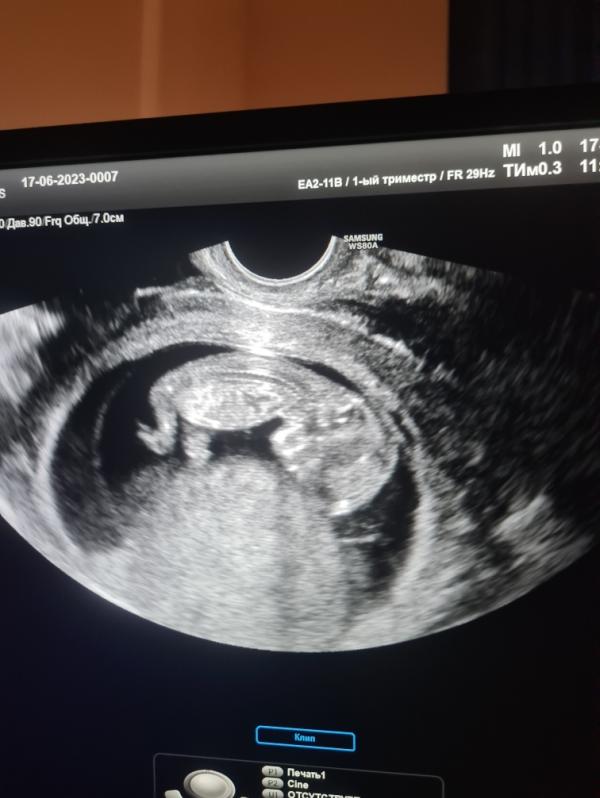

12 недель беременности: тонус матки, нормальная шейка, как дела у малыша? УЗИ и переживания

Мой маленький малыш❤️

Или малышка🥹

По подсчёта сегодня ровно 11 недель, но на узи скзаали все полные 12! Маковка, так быстро растет, мой человечек ❤️

По узи есть небольшой тонус, но шейка нормальная🥲